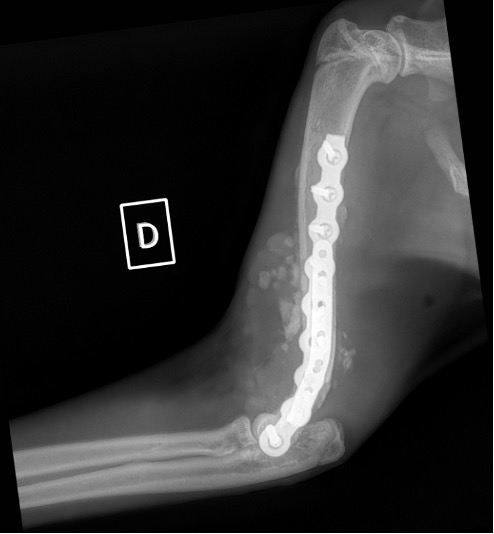

Exemple 3 :

Figure 9 : Pré-Op

Figure 10 : Opération

Figure 11 : Post-Op Immédiat

Figure 12 : Post-Op 1 mois